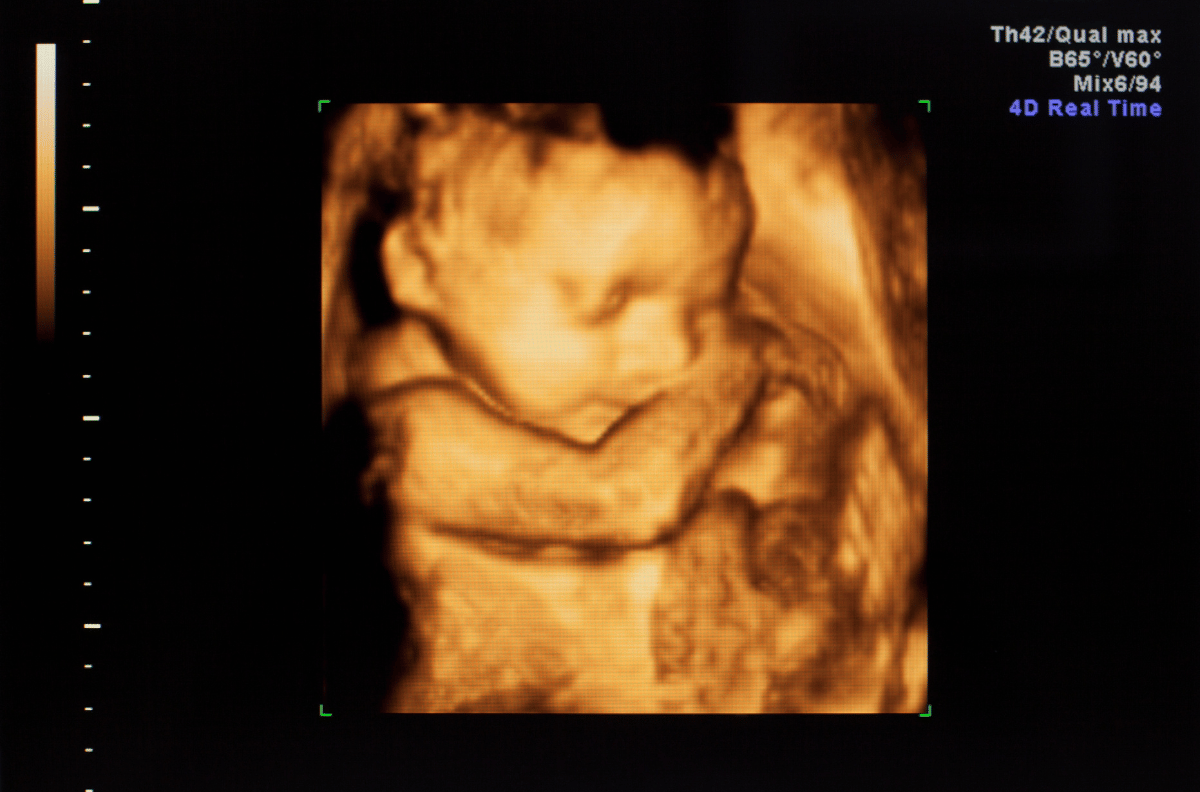

Além disso, realizamos exames laboratoriais e de imagem, incluindo exames de sangue, Doppler, eletrocardiograma, densitometria óssea, mamografia, ecocardiograma, biópsia e ultrassonografias (convencional, 3D e morfológica).

O ultrassom 3D é um exame de imagem que permite visualizar o feto em três dimensões.

é um exame de imagem que analisa a formação do bebê durante a gestação.